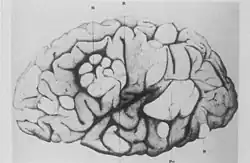

- French neurologist Désiré-Magloire Bourneville had a chance encounter with the disease that would bear his name. He was working as an unofficial assistant to Jean Martin Charcot at La Salpêtrière.[10] While substituting for his teacher, Louis J.F. Delasiauve,[12] he attended to Marie, a 15-year-old girl with psychomotor retardation, epilepsy and a "confluent vascular-papulous eruption of the nose, the cheeks and forehead". She had a history of seizures since infancy and was taken to the children's hospital aged three and declared a hopeless case. She had learning difficulties and could neither walk nor talk. While under Bourneville's care, Marie had an ever-increasing number of seizures, which came in clusters. She was treated with quinquina, bromide of camphor, amyl nitrite, and the application of leeches behind the ears. On 7 May 1879 Marie died in her hospital bed. The post-mortem examination disclosed hard, dense tubers in the cerebral convolutions, which Bourneville named Sclérose tubéreuse des circonvolutions cérébrales. He concluded they were the source (focus) of her seizures. In addition, whitish hard masses, one "the size of a walnut", were found in both kidneys.[13]